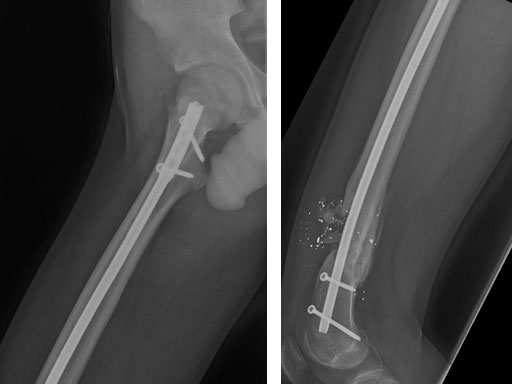

After stabilizing the fracture with an intramedullary nail (Fig 2) the patient was mobilized with weight bearing as tolerated. Uneventful healing and range of motion of the knee and functional ambulation returned to normal. Alignment of the fracture has been maintained with healing and maturation of callus processing as predicted. Blood supply to the proximal femur has been reserved with no signs of avascular necrosis. The ALFN's lateral entry point makes the nail insertion safer and diminishes the risk of circumflex artery injury.

Fig 2 Immediate postoperative AP x-ray.